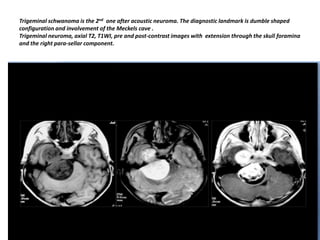

Trigeminal schwanoma is the 2nd one after acoustic neuroma. The diagnostic landmark is dumble shaped

configuration and involvement of the Meckels cave .

Trigeminal neuroma, axial T2, T1WI, pre and post-contrast images with extension through the skull foramina

and the right para-sellar component.